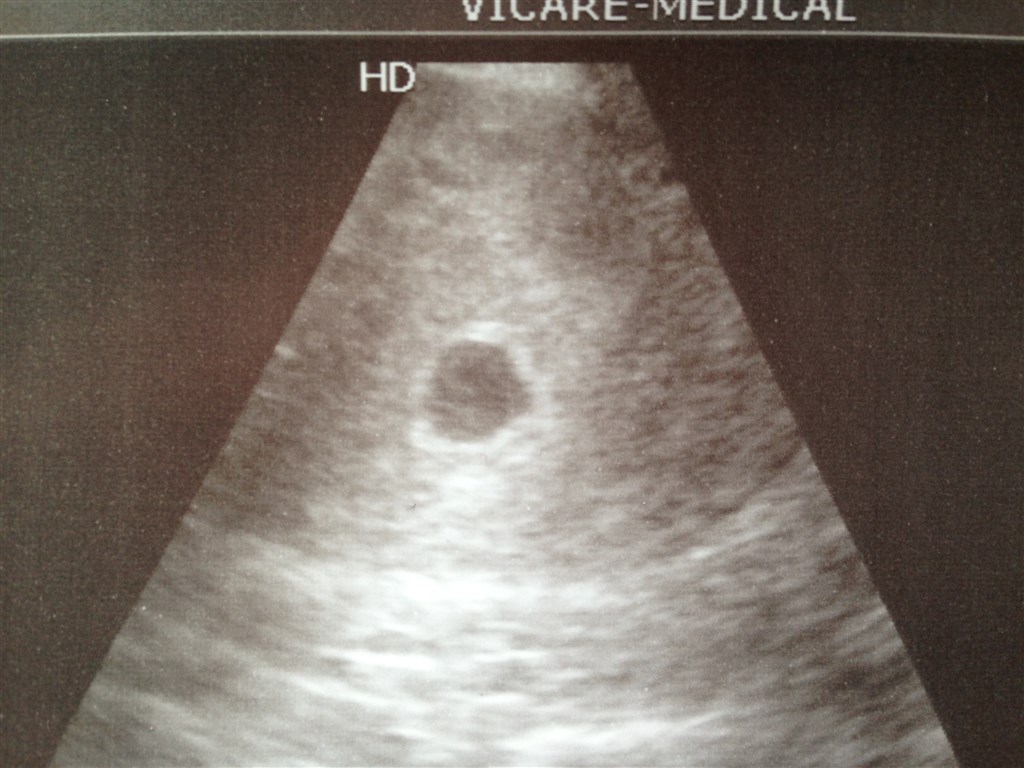

De kan se om det sidder som det skal, lægger billede ind fra min scanning i går, 5+3